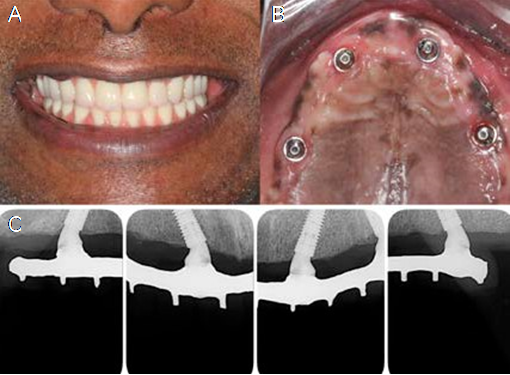

Due to the high initial implant stability obtained, it was possible to apply the immediate loading technique. Two GM Mini Conical Abutments of 30 degrees with 2.5mm transmucosal height (Neodent) were used on the implants of sites #15 and #25 and two GM Mini Conical Abutment of 17 degrees with 2.5mm transmucosal height (Neodent) were used in implants of sites #12 and #22 (Figure 3.B). The upper arch was sutured with 5.0 resorbable suture thread. Then, four open-tray impression copings were placed on the abutments and joined to the multifunctional guide in occlusion with the lower arch using Pattern acrylic resin (GC America Inc, Alsip, USA). The impression was performed with condensation silicone Speedex (Coltene, Altstätten, Switzerland) and sent to the prosthesis laboratory.

A passive fit technique was used to fabricate the prostheses. The mini abutment analogs (Neodent) were positioned in the transfers that were held in the impression material, and the definitive cast was obtained with artificial gingiva in place. Subsequently, the brass copings of the passive fitting technique (Neodent) were screwed to the analogs, and the castable coping was adapted over the brass ones. The framework was waxed and then soldered and adapted onto the brass copings of the working cast. The prosthetic teeth were mounted according to the intraoral clinical evaluation. The prosthesis was processed. The brass copings were removed and titanium copings (Neodent) were screwed into the working cast. The access holes were sealed, and the framework was cemented over the titanium copings with an adhesive resin cement (Panavia; Kuraray America Inc.) (11). This technique compensates for any distortion inherent in 1-piece castings by luting the framework to the titanium cylinder, which has a smalle dimension than the brass coping used during the framework waxing (12). The prosthesis was finished. Although it was screw retained, a precise fit was achieved because the cement compensated for any casting distortions. After 24 hours, the patient returned with good healing of the upper arch (Figure 3.C) and a try-in of the teeth fixed with wax to the metal bar was performed.

Forty-eight hours thereafter, the teeth were tried in, fixed with wax to the metal bar and on the third day the final prosthesis was inserted, according to the passive fit technique. Occlusal adjustments were performed, relieving excessive contact in excursive movements during the osseointegration period, but keeping the prosthesis in occlusion (Figure 4.A, Figure 4.B and Figure 5).

The patient returned with 14 days post-surgery to remove the suture and assess the clinical and radiographic condition of the rehabilitation. After 30 days and 6 months, success of implants and rehabilitation, favorable remodeling of the peri-implant tissues and satisfactory aesthetic and functional conditions were observed (Figure 6 and Figure 7).